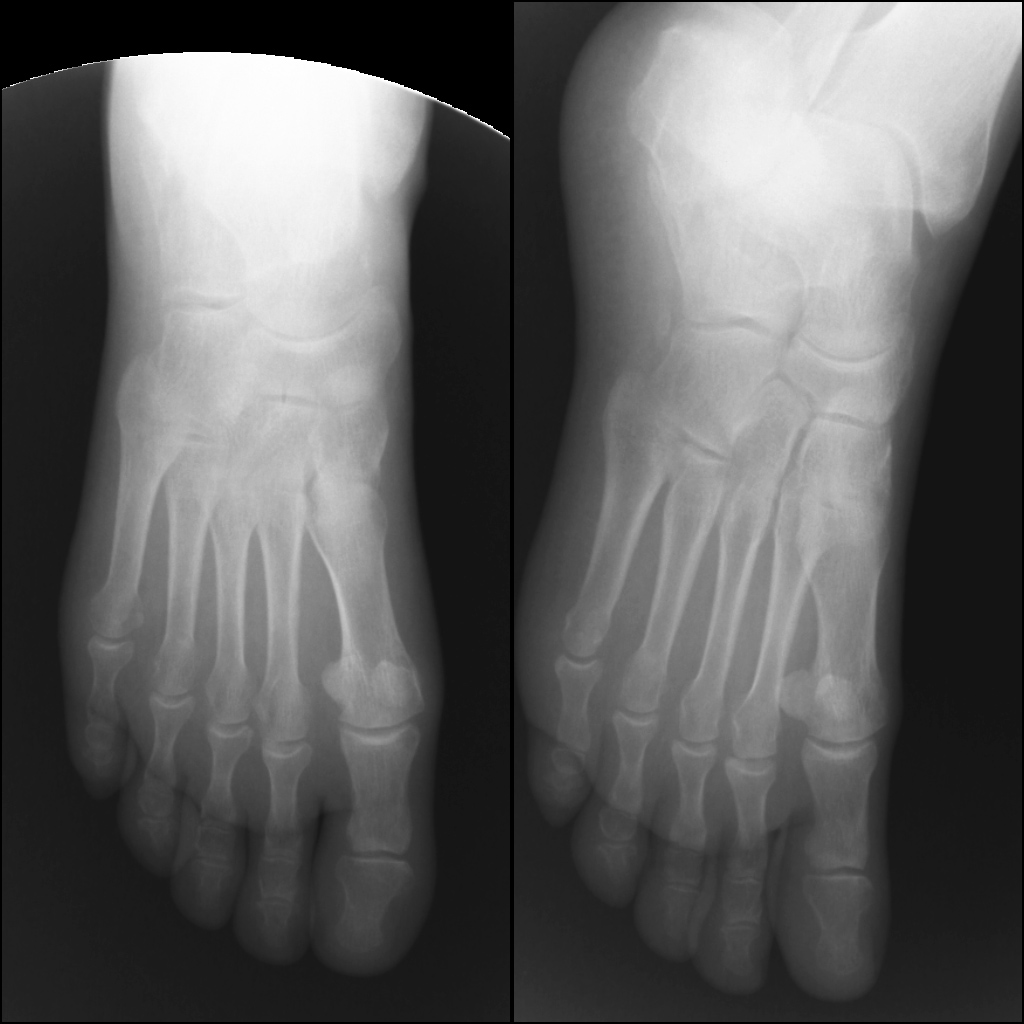

Женщина, возраст 55 лет.,вес 60кг.11.11.13 Падение с высоты 3х метров на ногу. сильная гематома на внутренней и внешней поверхности стопы. При первичном осмотре в республиканской больнице (г.Сухум) установлен диагноз: ушиб. Пациент отпущен домой.28.11.13 Сильные боли в течение двух недель.Сделан повторный рентген. Гематома спала, но полностью не рассосалась, боли уменьшились. Вторичный осмотр в военном госпитале (г.Агудзера).Диагноз: Осколочный перелом пятки со смещением.Лечение: Наложен гипс.Снимки прилагаю. Прошу помощь, по возможности, определить точность диагноза и лечения. Спасибо.

Снимок №3

Кликните для загрузки файла 1.jpg

Перелом пятки. Если есть возможность сделать малоинвазивный остоетсоинтез - то сделать, если нет - можно и консервативное, результат должен быть удовлетворительный.